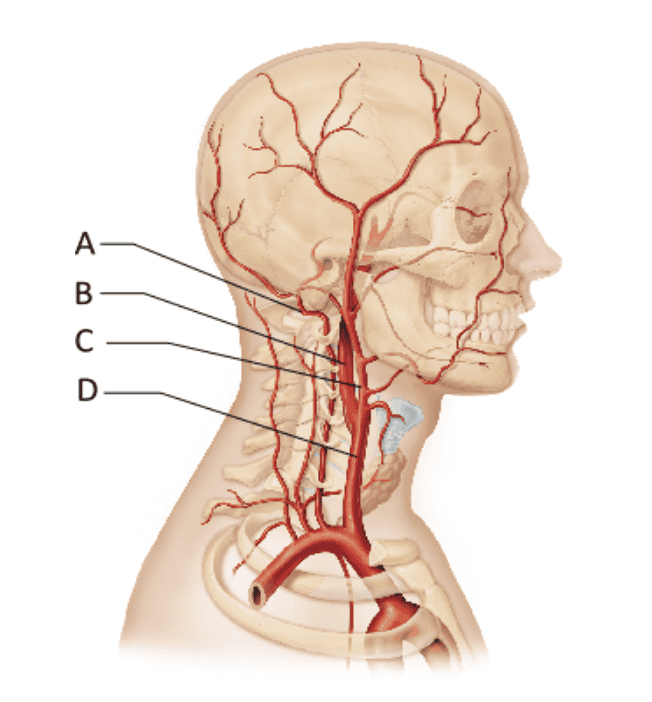

Which artery branches off the subclavian arteries?

- A

- B

- C

- D

A

Ex.

The vertebral arteries, which travel up the spinal column via the transverse foramina of the cervical bones, arise from the subclavian arteries.